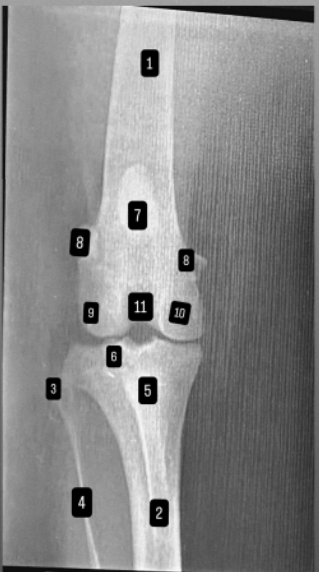

podaj elementy od 1 -11

czym jest zwichnięcie rzepki?

jest to przemieszczenie na stronę przyśrodkową lub boczną poza odpowiednią krawędź bloczka (grzebienia) kości udowej, najczęściej stan ten stwierdza się u psów małych ras, właściciele zgłaszają się do lekarza z powodu kulawizny którejś z tylnych kończyn (przemieszczenie rzepki poza bloczek) u ras dużych statystycznie częściej się rzepka przemieszcza na stronę boczną u małych na przyśrodkową